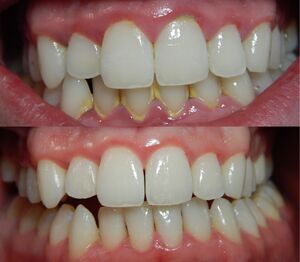

Gingivitis before (top) and after (bottom) a thorough mechanical debridement of the teeth